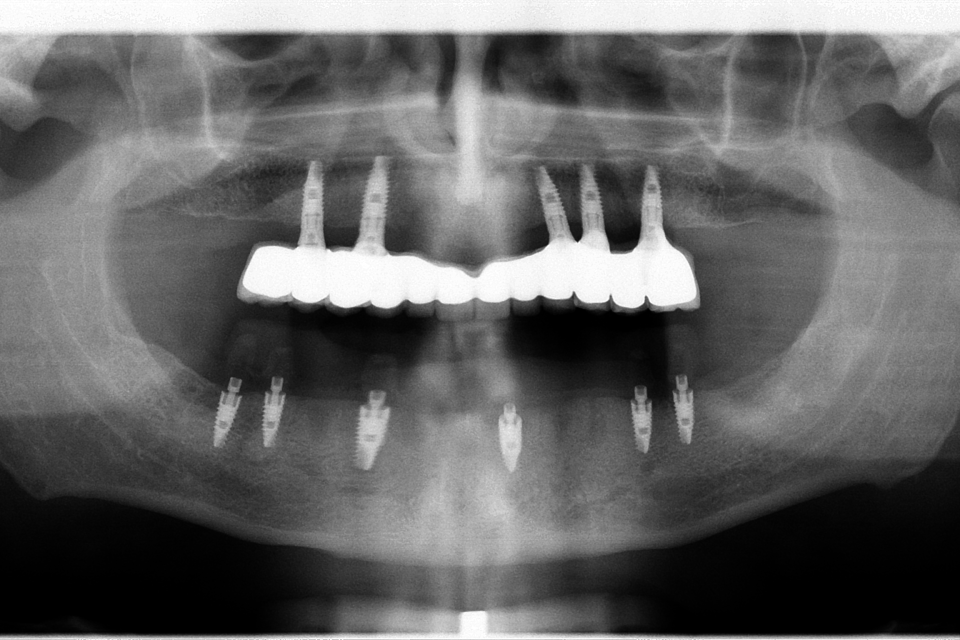

Pacient prezentat in cabinet cu boala parodontala cronica profunda generalizata, toti dintii prezentand mobilitate parodontala grad 3 din 3. Impreuna cu pacientul am decis extragerea tuturor dintilor la maxilar si inserarea implanturilor dentare, care au fost initial incarcate provizoriu, iar dupa 3 luni au fost protezate cu o lucrare metalo-ceramica fixa.

In cazul mandibulei au avut loc extractii, chiuretarea pungilor parodontale, inserarea postextractionala a 6 implanturi Paltop si s-a realizat in aceeasi zi o lucrare provizorie acrilica, cu care am restaurat functionalitatea aparatului dento maxilar urmand ca dupa 3 luni, dupa osteointegrarea finala a implanturilor sa concepem lucrarea finala.